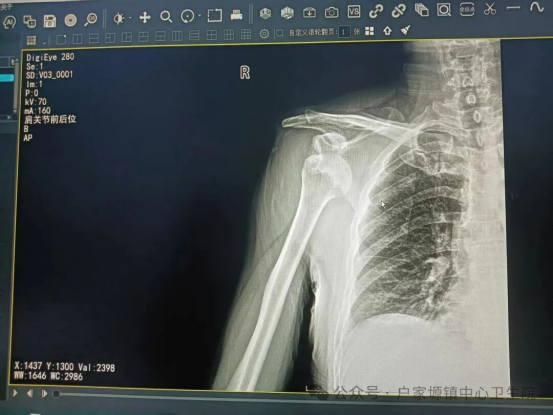

患者就诊时,肩关节明显畸形、疼痛剧烈,活动完全受限,情绪十分焦虑。接诊医生立即对患者进行详细查体及影像学检查,明确诊断为新鲜肩关节脱位,排除骨折、神经血管损伤等禁忌证后,迅速通知我院外科团队,制定了安全高效的手法复位方案。